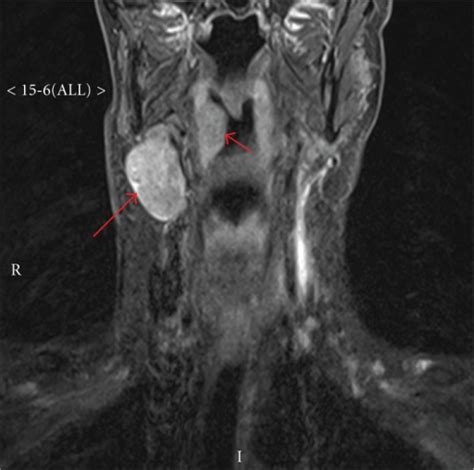

Ultrasound imaging: Normal and enlarged lymph nodes: from 1.bp.blogspot.com A neck ultrasound may help diagnose (find): The image may or may not suggest cancer, but definitive diagnosis requires removal of. A thyroid ultrasound may be ordered if a thyroid function test is abnormal or if you doctor feels a growth on your thyroid while examining your neck. Ultrasound is relatively quick and simple test that gives very useful information about the soft tissues in the head and neck region including the lymph glands, salivary glands, thyroid gland and any abnormal lumps. It can be used to help diagnose a wide range of medical conditions affecting the thyroid gland, including benign thyroid nodules and possible thyroid cancers. While it can't diagnose cancer, it can detect the abnormal tissues that may possibly be cancerous. Imaging tests show pictures of the inside of the body. If this lump is of concern then a biopsy would be the next step.

Throat cancer is often easily seen by an ent exam. Ultrasound is used to see the thyroid or the lymph node (s) during the biopsy, which helps make sure they are getting fna samples from the right areas. A neck ultrasound may help diagnose (find): If an ultrasound would image a tumor in the throat as well as the neck above the collar bone it would be pointless to have another procedure done. When ultrasound is performed on a patient with nodular goiter, or a patient with a history of thyroid cancer, finding a prominent lymph node with a rounded shape (long/short axis ratio < 2) and absent hilar line warrants further evaluation of the node (figs. Thyroid nodules that are hypervascular, hypoechioc, or contain calcifications on ultrasound are more likely to be malignant. Your two carotid arteries are located on each side of your neck. An ultrasound can also check an underactive or. For most types of cancer, a biopsy is the only sure way for the doctor to know if an area of the body has cancer. Lymph nodes are part of the lymphatic system, which helps to protect us from infection and disease. In this type of scan, doctors use a small camera to look at the body organs. If this lump is of concern then a biopsy would be the next step. A thyroid ultrasound may be ordered if a thyroid function test is abnormal or if you doctor feels a growth on your thyroid while examining your neck.

Lymph nodes in the neck from thyrosite.com I was officially diagnosed hashimoto's by my endocrinologist 2 weeks ago but she has refused to do an ultrasound of the thyroid. Ultrasound guidance is used to perform thyroid biopsies and improves the diagnostic accuracy of fine needle biopsy. A neck ultrasound can be used to observe the thyroid gland to look for nodules, growths, or tumors. Doctors may also do tests to learn which treatments could work best. A neck ultrasound may help diagnose (find): However if the ultrasound would be limited to the neck and not the actual throat i'd have the endoscopy done. Doctors often use ultrasound to guide a needle to do a biopsy (taking out fluid or small pieces of tissue to be looked at under a microscope). This test uses sound waves to produce a picture of your neck and lymph nodes on a computer screen.

An ultrasound scan of the neck uses sound waves to build up a picture of your neck and lymph nodes.